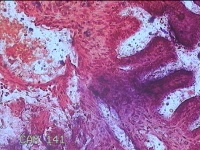

右侧输卵管赘生物

性别

女

年龄

25岁

临床诊断

一般病史

停经3个月,下腹胀痛伴阴道流血3天。

标本名称

大体所见

灰白暗红色肿物0.8x0.7xcm一个,表面糜烂。